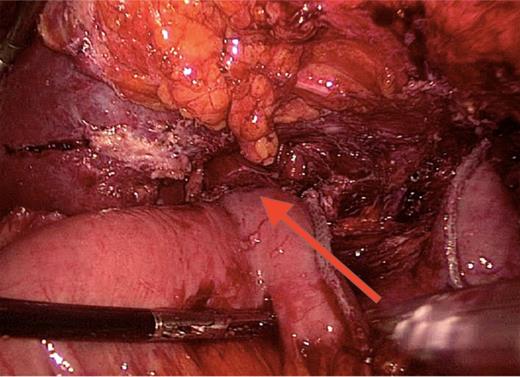

After a multicentre complex benign oesophago-gastric multidisciplinary team (MDT) discussion, indication for a total gastrectomy was given. On 12 January 2015, patient underwent a laparoscopic completion of gastrectomy and Roux-en-Y oesophago-jejunostomy (Fig. 5). GS a week later showed no leak. The patient recovered well with no complication. At last follow-up, she remained well.

Roux-en-Y reconstruction. Laparoscopic total gastrectomy performed 5 years after the sleeve gastrectomy. Oesophago-jejunal anastomosis is indicated by the arrow.